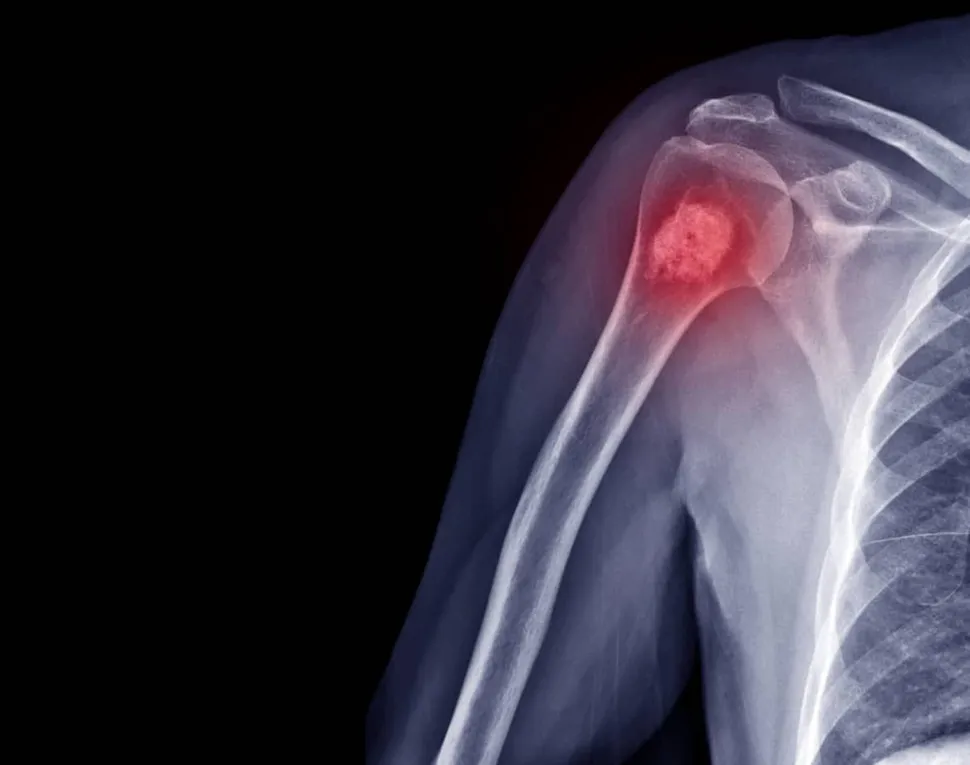

In “Myeloma 101” we learn, “Multiple myeloma is a cancer of the plasma cell, a type of white blood cell present in the bone marrow that makes antibodies to fight infection. In patients with myeloma, plasma cells proliferate too rapidly, crowding out healthy cells and causing painful areas of bone damage called osteolytic lesions.”